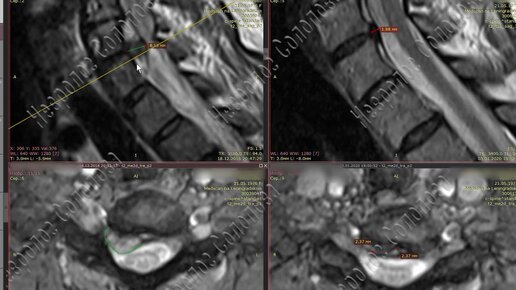

Результат лечения огромной грыжи 8 мм в шейном отделе